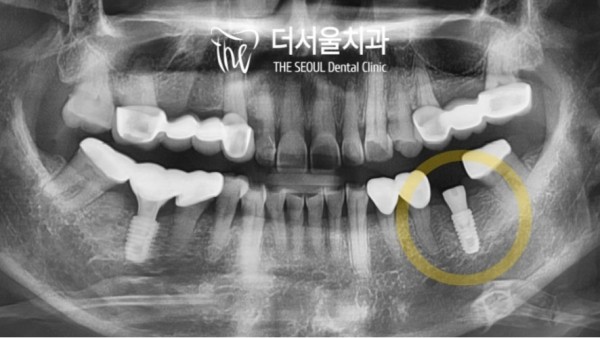

36번을 보시면 빈공간이 보이는데요.

35번과 37번을 지대치로 브리지를 하셨던 부분입니다.

다른 치아는 지대치였던만큼 치근이 남아있지만 36번은 아예 치아가

상실된지 오래된 공간이었습니다.

이렇게 오랜시간 치아를 상실한채로 빈공간으로 두게되면

치조골이 소실되어 임플란트를 심기 어려워질 수 있습니다.

태평역치과 더서울치과의 디지털내비게이션 분석을 통해

환자분의 임플란트 계획을 최대한 안전한 선까지 확인을 하였는데

8.5mm로 디자인을 한뒤 위와같이 심으면 신경과의 거리로 인한

문제가 발생되지 않을것으로 확인되었습니다.